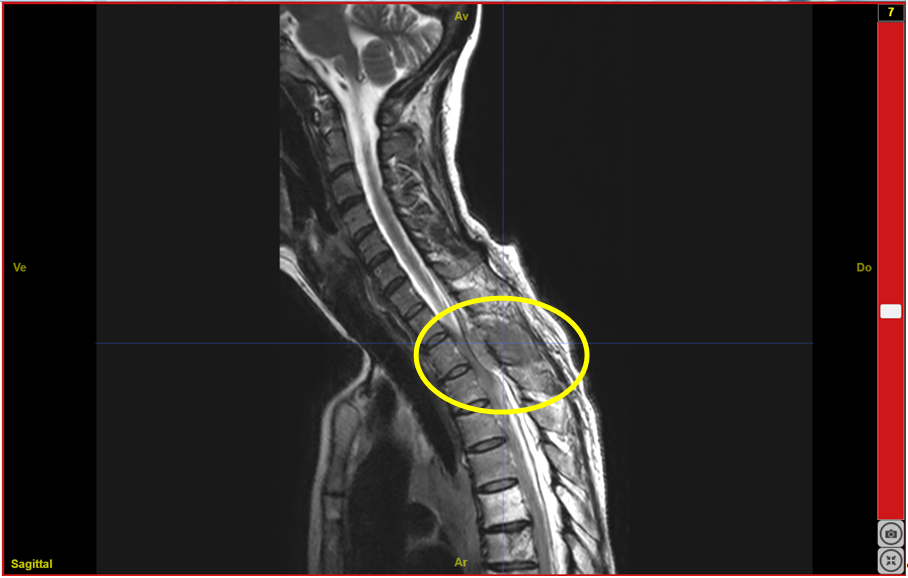

IRMsujet122421PathologieMedullaireCompressionT2T3.anat.nii.gz